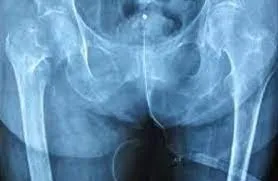

Οι ερευνητές, με επικεφαλής τη δρα Αν-Φρεντερίκ Τιρκότ της Μονάδας Ενδοκρινολογίας και Νεφρολογίας του Κέντρου Ερευνών του Κεμπέκ, που έκαναν τη σχετική ανακοίνωση στο ετήσιο Ευρωπαϊκό Συνέδριο για την Παχυσαρκία στο Μάαστριχτ της Ολλανδίας, ανέλυσαν στοιχεία για σχεδόν 20.000 ανθρώπους 40 έως 70 ετών. Σε βάθος περίπου έξι ετών, 497 γυναίκες και 323 άνδρες έπαθαν κάποιο κάταγμα. Από αυτά, τα 415 οφείλονταν σε οστεοπόρωση (260 σε γυναίκες και 155 σε άνδρες).

Διαπιστώθηκε ότι για κάθε αύξηση κατά πέντε εκατοστά στην περιφέρεια της μέσης μιας γυναίκας λόγω έξτρα κιλών, ο κίνδυνος κατάγματος αύξανε κατά 3% έως 7%, ανάλογα με το σημείο του σώματος. Όσο μεγαλύτερο ήταν το σωματικό βάρος μιας γυναίκας, τόσο περισσότερο αυξημένος ήταν ο κίνδυνος κατάγματος.

Στους άνδρες ούτε το αυξημένο βάρος ούτε ειδικότερα το συσσωρευμένο πέριξ της μέσης πάχος εμφανίζουν σημαντική συσχέτιση με τα κατάγματα. Από την άλλη, ένας άνδρας με βάρος κάτω του κανονικού (με δείκτη μάζας σώματος μικρότερο του 17,5) έχει διπλάσια πιθανότητα να πάθει κάταγμα στο άνω άκρο, σε σχέση με έναν άνδρα με δείκτη μάζας σώματος 25 (το ανώτερο κανονικό).